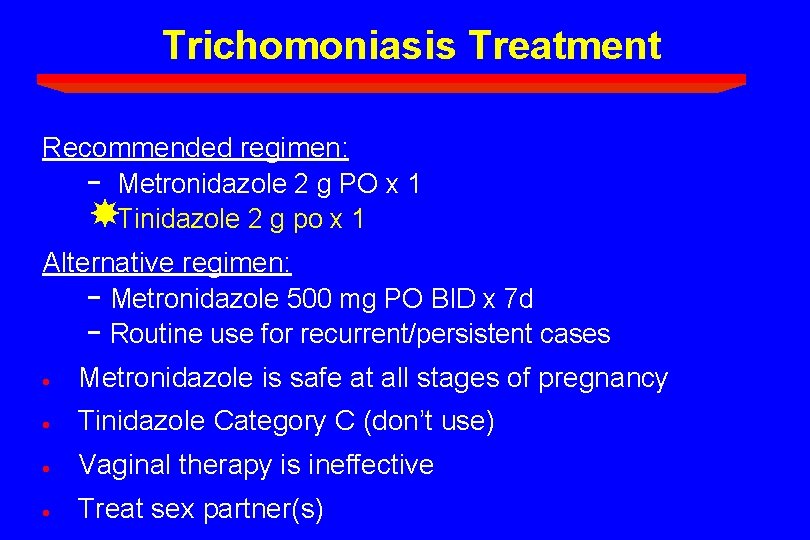

Trichomoniasis Treatment Recommended regimen: - Metronidazole 2 g PO x 1 Tinidazole 2 g po x 1 Alternative regimen: - Metronidazole 500 mg PO BID x 7 d - Routine use for recurrent/persistent cases · Metronidazole is safe at all stages of pregnancy · Tinidazole Category C (don’t use) · Vaginal therapy is ineffective · Treat sex partner(s)